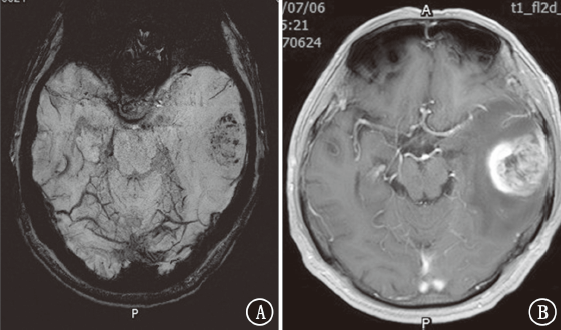

目的探讨磁敏感加权成像(SWI)在颅内转移瘤中的鉴别诊断价值。方法收集2018年 1月至2020年4月新疆维吾尔自治区人民医院住院患者中原发肿瘤为肺癌、乳腺癌、肾癌、直肠癌、膀胱癌、黑色素瘤的颅内转移瘤及胶质母细胞瘤患者63例,半定量评估肿瘤内的敏感性信号强度(ITSS)分级。比较颅内转移瘤与胶质母细胞瘤ITSS分级。结果81个颅内转移瘤中,0级为36个(44.4%),Ⅰ级为25个(30.9%),Ⅱ级为14个(17.3%),Ⅲ级为6个(7.4%);27个胶质母细胞瘤均为Ⅱ~Ⅲ级(100%)。肺癌转移瘤0~Ⅰ级占73.6%(28/38),乳腺癌转移瘤0级占84.6%(22/26),肾癌转移瘤Ⅱ级占5/6,直肠癌转移瘤0~Ⅰ级占4/5,胶质母细胞瘤Ⅲ级占77.8%(21/27)。颅内转移瘤与胶质母细胞瘤ITSS分级组间差异有统计学意义(Z=7.013,P<0.001)。采用受试者工作特征曲线分析显示,ITSS≤Ⅰ级判断颅内转移瘤的敏感性为100%,特异性为75.3%,曲线下面积为0.936(95%CI为0.891~0.980,P<0.001)。结论颅内转移瘤ITSS分级多表现为0~Ⅰ级,胶质母细胞瘤多表现为Ⅱ~Ⅲ级。SWI在颅内转移瘤中有一定的鉴别诊断价值。

ObjectiveTo explore the value of susceptibility weighted imaging (SWI) in differential diagnosis of intracranial metastatic tumors.MethodsSixty-three patients with intracranial metastatic tumors (primary tumors of lung cancer, breast cancer, kidney cancer, rectal cancer, bladder cancer and melanoma) and glioblastomas in People's Hospital of Xinjiang Uygur Autonomous Region from January 2018 to April 2020 were collected, and the intratumoral susceptibility signal intensity (ITSS) was evaluated semi-quantitatively. The grading characteristics of ITSS of metastatic tumors and glioblastomas were compared.ResultsAmong the 81 intracranial metastatic tumors, 36 (44.4%) were grade 0, 25 (30.9%) were grade Ⅰ, 14 (17.3%) were grade Ⅱ and 6 (7.4%) were grade Ⅲ. Among the 27 glioblastomas, 27 (100%) were grade Ⅱ-Ⅲ. Grade 0-Ⅰ metastatic tumors of lung cancer accounted for 73.6% (28/38). Grade 0 metastatic tumors of breast cancer accounted for 84.6% (22/26). Grade Ⅱ metastatic tumor of kidney cancer accounted for 5/6. Grade 0-Ⅰ metastatic tumors of rectal cancer accounted for 4/5. Grade Ⅲ glioblastomas accounted for 77.8% (21/27). The difference of ITSS classification between intracranial metastatic tumors and glioblastomas was statistically significant (Z=7.013,P<0.001). According to the receiver operating characteristic curve analysis, the sensitivity and specificity of ITSS ≤grade Ⅰ were 100% and 75.3% respectively, and the area under the curve was 0.936 (95%CI: 0.891-0.980,P<0.001).ConclusionThe patients with intracranial metastatic tumor usually present ITSS grade 0-Ⅰ, and the patients with glioblastoma usually present ITSS grade Ⅱ-Ⅲ. SWI has a certain value for differential diagnosis of intracranial metastatic tumors.